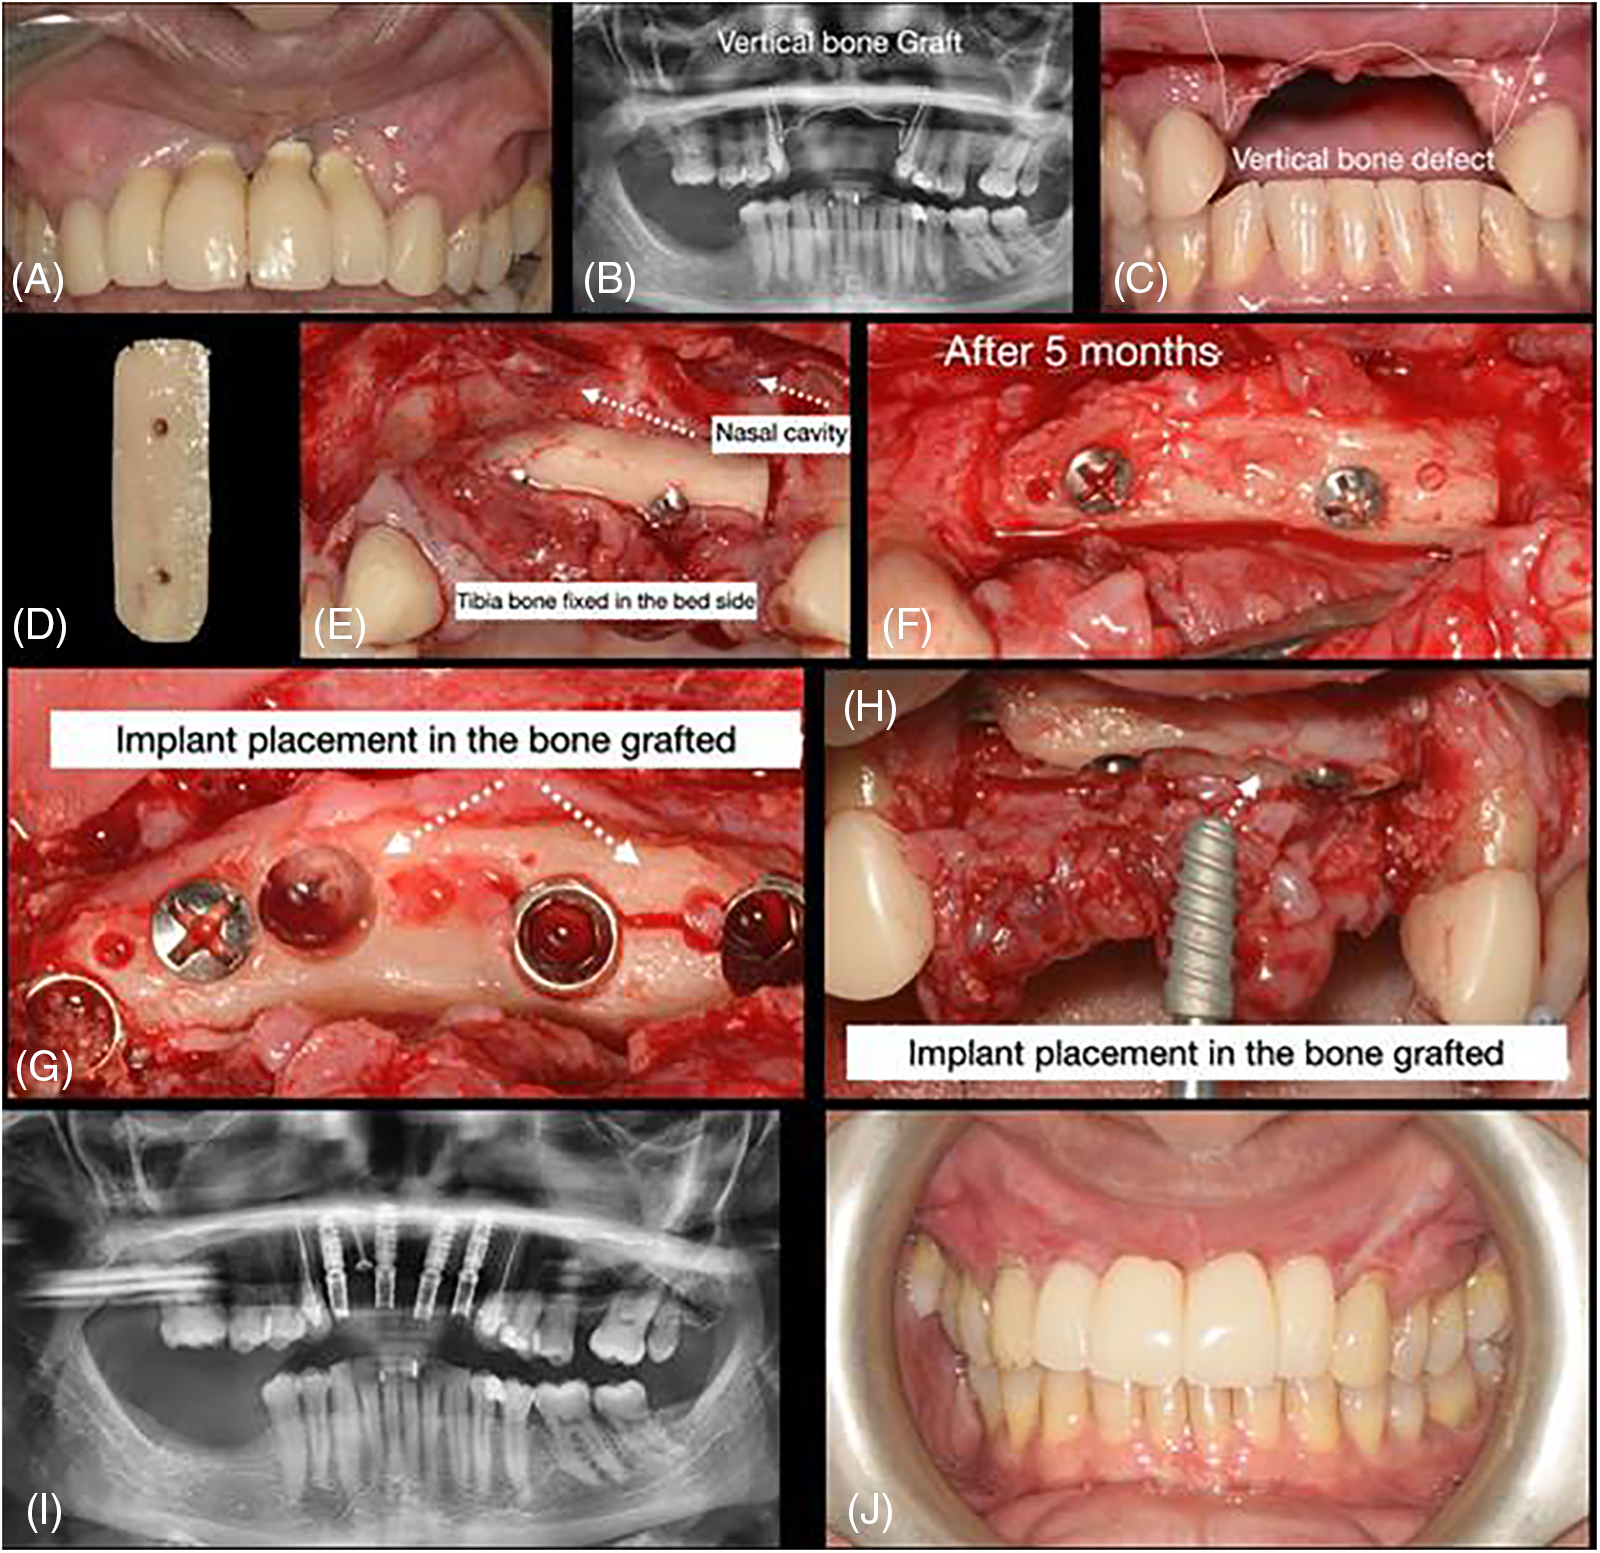

Figure 2: Case 2. Sequential images for the treatment: (A–C) initial clinical presentation and panoramic exam (with and without the old prosthesis); (D) bone block prepared; (E) surgical placement of the block bone graft; (F) surgical approach for block bone graft installation; (G–H) flap raised to expose the block after 5 months and 15 days. Sample collected and implant placement (observed the presence of a small fracture in the block); (I) new panoramic after implants placed; and (J) final rehabilitation after 6 months of the implant placement

The cases were performed following the same sequence, varying the quantity and size of bone used to reconstruct but always keeping the same type of donor region (tibia), e.g., Fig. 1 shows 2 block bone grafts, and Fig. 3 with three blocks. Figs. 1–3 show the procedures done in all of them. Initially, a panoramic X-ray was requested for the primary assessment and overview (Figs. 1 and 2). CBCT was sequentially assessed to verify the necessary dimensions and volume of the bone graft. The surgery was scheduled after receiving the bone graft, and the surgical guide for the implant placement was prepared (Figs. 3 and 8).

The flap was raised according to the needed extension, and the receptor bedside was prepared to receive the homologous bone graft from the tibia. The block graft had an adequate cortical width (≥5 mm), length, height, and medullar area. After adjustments, the homologous bone was fixed using at least 2 screws, transfixing both cortical (buccal and lingual) of the bedside receptor. The immediate osseous volume obtained during the surgery was adequate for posterior rehabilitation (Figs. 1–8); therefore, after the healing period (between 5 and 12 months), a volume loss was expected and found due to tissue remodeling (Fig. 8). After the healing period, the patients were recalled for a new evaluation and panoramic/CBCT analysis (Figs. 1 and 2). Afterward, the surgical procedure for implant placement was scheduled, where the block was trephined to obtain the samples for histological processing (Figs. 1–3 and 8; macroscopic aspects of the histological piece [4 ø mm × 4 mm height]). The implant placement occurred without a significative event, except in one case, in which a small fracture in the block graft was observed (Fig. 2) during the implant installation (after healing); this fact did not harm the procedure and rehabilitation.